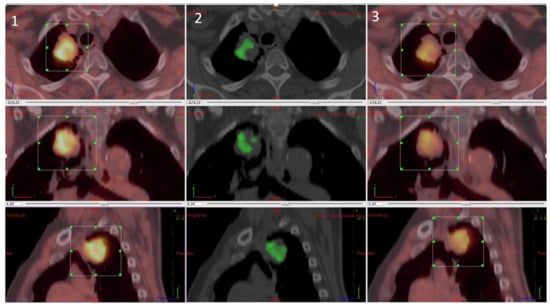

4.2. PET Results

4.3. Overlap Fraction, Parametric Results, and Immunohistochemistry Results